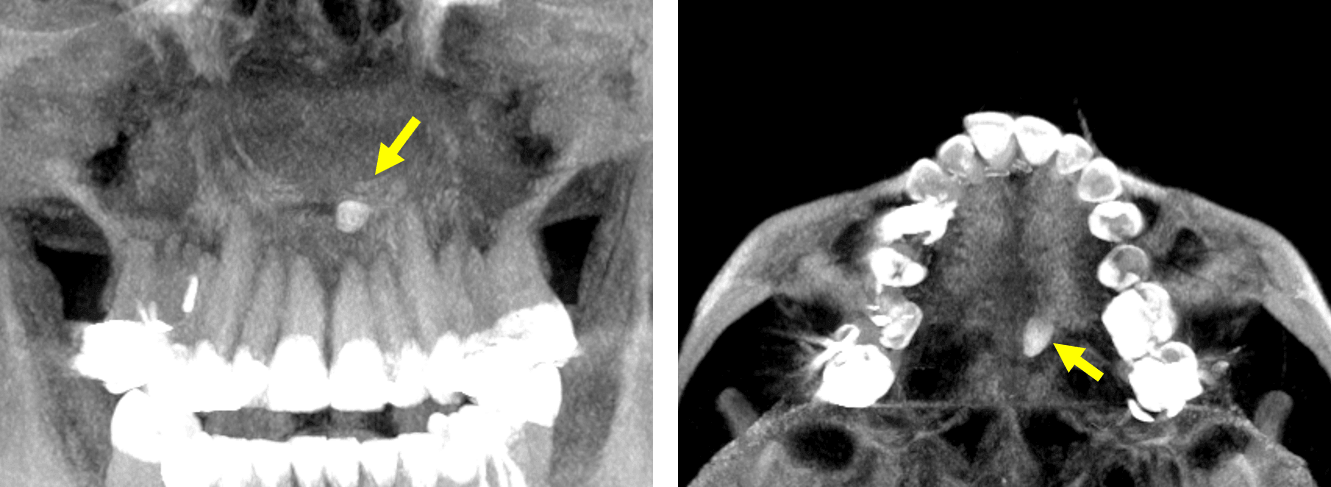

Fig.1

En la evaluación tomografía computarizada cone beam, se realizaron los cortes sagitales (Fig.1) la presencia de un objetó de densidad dentaria a nivel de la placa horizontal del hueso palatino, que se articula con la apófisis palatina del maxilar superior, que compromete la cortical superior e inferior.

Fig.2

En cortes coronales (Fig.2) se observa que el objeto identificado en el paladar se observa orientado hacia el lado izquierdo de la zona medial, a nivel del cortical superior que compromete que compromete el piso de la fosa nasal izquierda.

Fig.3

En cortes axiales (Fig.3), se observa que se trata de un diente supernumerario, evidenciando una forma cónica orientado hacia el lado izquierdo de paladar.

Fig.4

En la representación tridimensional (Fig.4) en proyección de máxima intensidad, se observa la densidad dentaria antes mencionada, tratándose de un diente supernumerario compatible con Mesiodens.